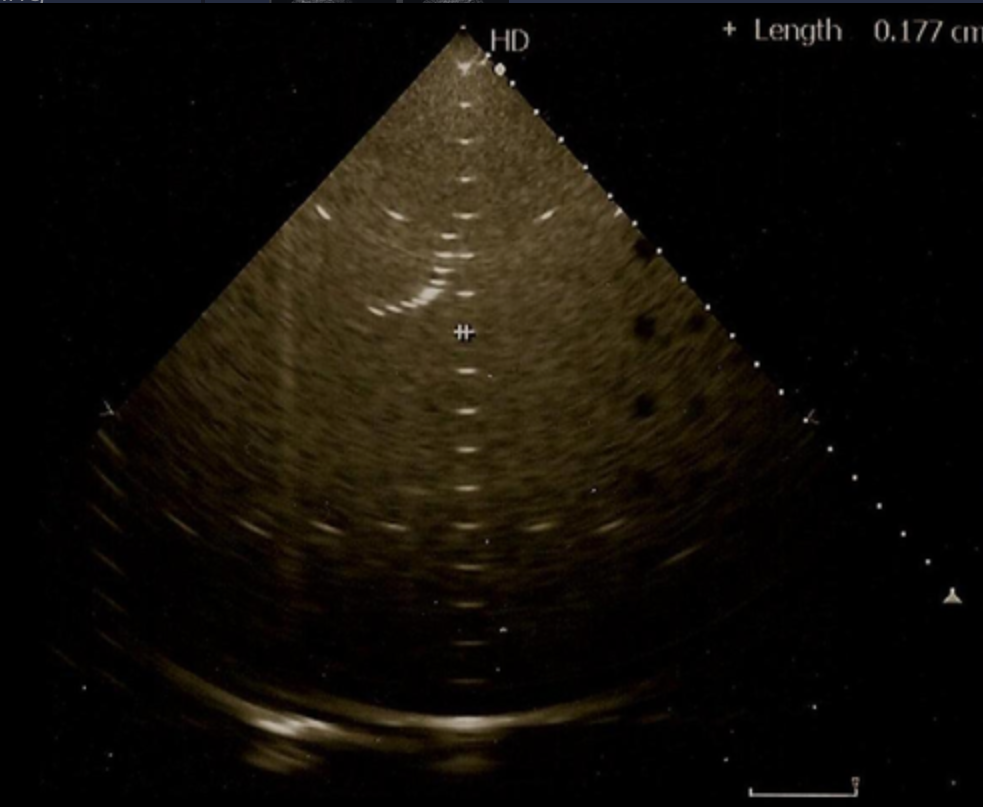

What system parameter is being assessed on the phantom image?

a. lateral resolution

b. axial resolution

c. horizontal distance calibration

d. depth calibration

lateral resolution